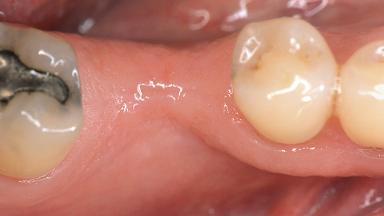

Soft-Tissue Volume Augmentation Using a Connective-Tissue Graft Harvested from the Maxillary Tuberosity

Soft Tissue Grafting Simultaneous

Soft Tissue Anatomy Intact Defective